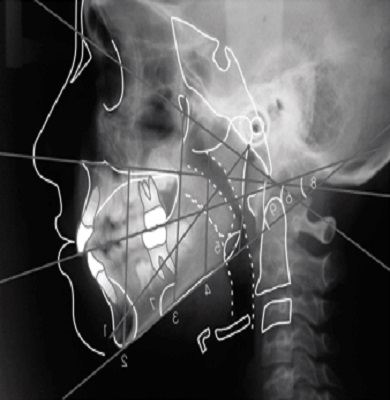

Wilhelm Conrad Röntgen’in 1895’te X ışınlarını bulması, tıbba ışınım tedavisi (radyoterapi) gibi yeni olanaklar sağlamakla kalmamış, cerrahide bir dönüm noktası olmuştur. İdrar ve safra kesesi taşlarının, vücuttaki bir merminin ya da yabancı bir cismin, urların yerinin önceden belirlenmesi, kırıkların X ışınlarıyla incelenmesi cerrahi girişimin başarı şansını artıran önemli bir etken oldu. 1927’de Lizbon Üniversitesinden Antonio Egas Moniz, kan damarlarına X ışınlarını geçirmeyen kontrast madde vererek, beyindeki atardamarların röntgen filmini çekmeyi başardı. 1938’de ABD’li George Porter Robb ve Israel Steinberg, atar ya da toplardamarlardan kalbe ince bir boru (kateter) sokarak, kalp odacıklarının X ışınlarıyla incelenmesine öncülük ettiler.